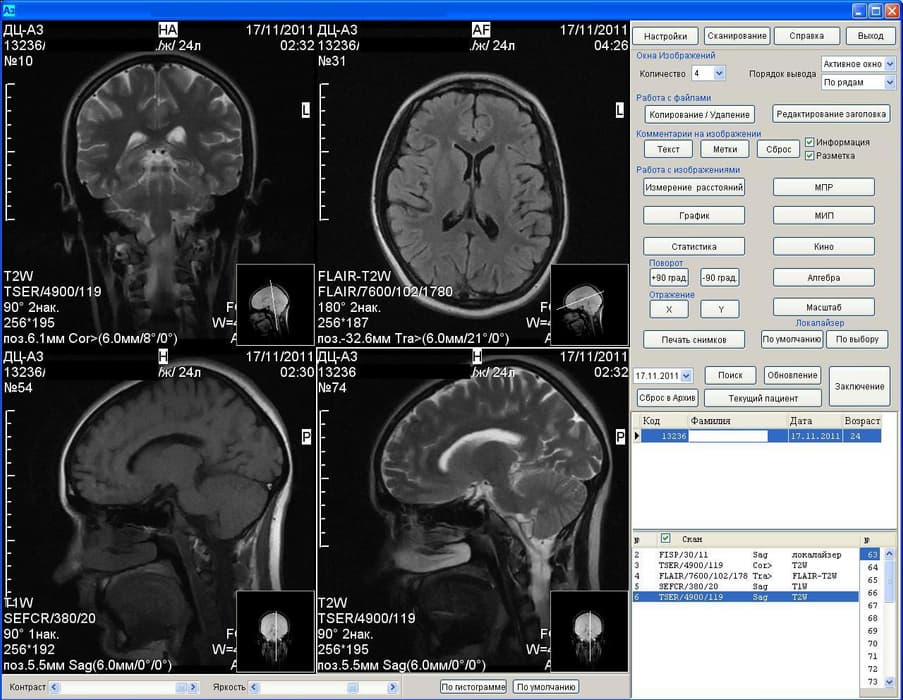

Результаты аппарата МРТ Аз-300

Отмечается, что ученые восстановили функциональные сети головного мозга здоровых людей и пациентов с депрессией. Методика, получившая название «консенсусный подход», выявила различия в результатах функциональной МРТ у двух групп людей.